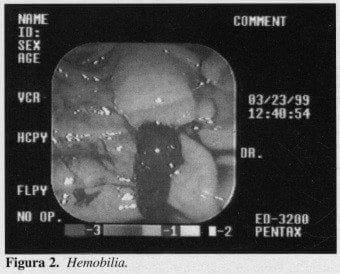

Los pacientes correspondían según el sexo a 146 mujeres (60.8%), y 94 hombres (39.2%); las edades fluctuaron entre 24 y 93 años con un promedio de 62.4 años. Los tiempos endoscópicos para lograr un adecuado diagnóstico y terapéutica fueron para 1 solo tiempo, 208 (86.67%), 2 tiempos 27 (11.25%) y 3 tiempos 5 (2.08%); el lapso entre uno y otro procedimiento fue de 48 horas siempre, tiempo que se considera necesario para lograr disminución del posible edema por trauma local y la eventual necrosis del tejido que puede comprometerse en una infundibulotomía o papilotomía parcial, lo que permite en un segundo intento canalizar fácilmente la vía biliar principal (Tabla 1), (Figura 1).

Las esfinterotomías endoscópicas, 139 de las cuales fueron exitosas. 128 (92.08%); fallidas, 11 (7.91%) (Tabla 3).